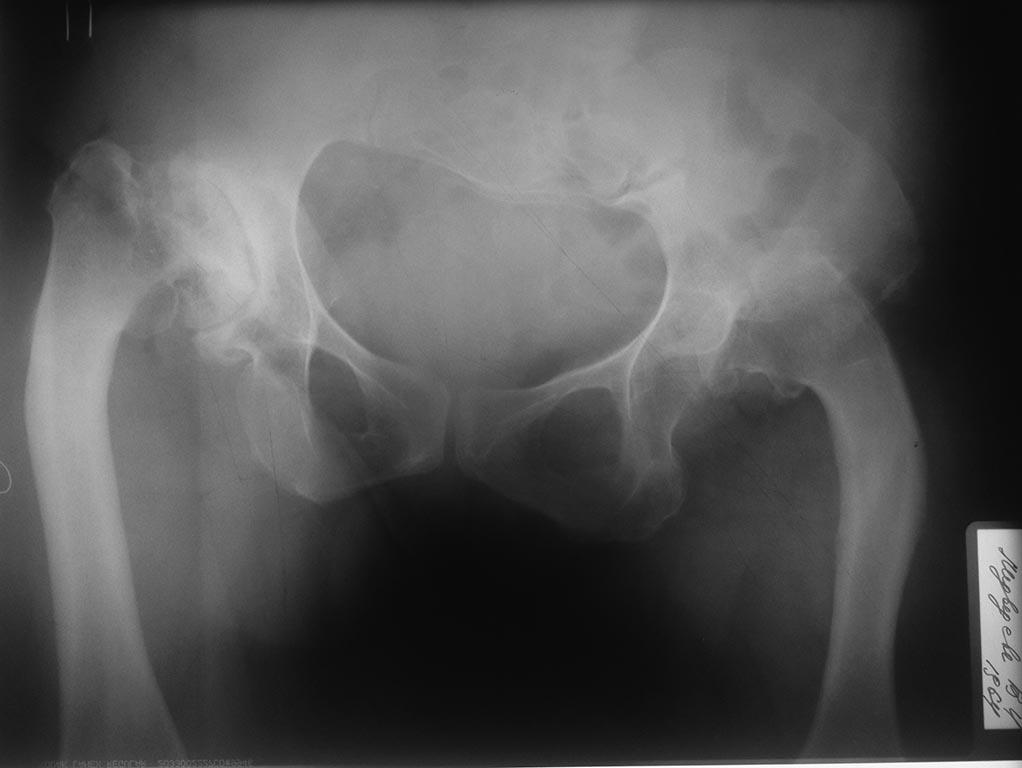

Здравствуйте, коллеги! Планируется эндопротезирование суставов у пациентки с врожденной аномалией развития скелета Пациентка 48 лет, врожденная аномалия скелета. В настоящее время поступила с диагнозом:Диспластический коксартроз III ст справа, вывих левого бедра (Crowe IV). Гонартроз слева III. Варусные деформации обоих бедер. Сгибательная, приводящая, ротационная контрактура правого тазобедренного сустава. Сгибательная контрактура левого коленного сустава. Из анамнеза: Больна с детства, в возрасте 15-17 лет субспинальные миотомии с обеих сторон, отсечение большого вертела слева дополненное скелетным вытяжением.Планируется: Первым этапом эндпротезирование правого тазобедренного сустава с одномоментной коррекцией варусной деформации. Вторым этапом эндопротезирование слева с укорачивающая и корригирующей остеотомией. Третий - левый коленный сустав. У кого есть опыт протезирования подобных пациентов, прокоментируйте пожалуйста. Может что недооцениваем.